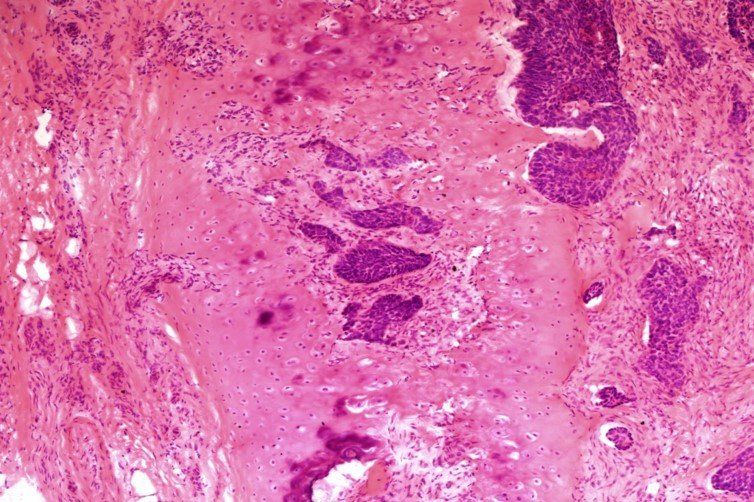

H+E - BMT Scheme

Seen at x20. Overall a very good preperation, but marks were deducted for folds and creases, loss of material, and haematoxylin background staining. This slide scored 8/10.